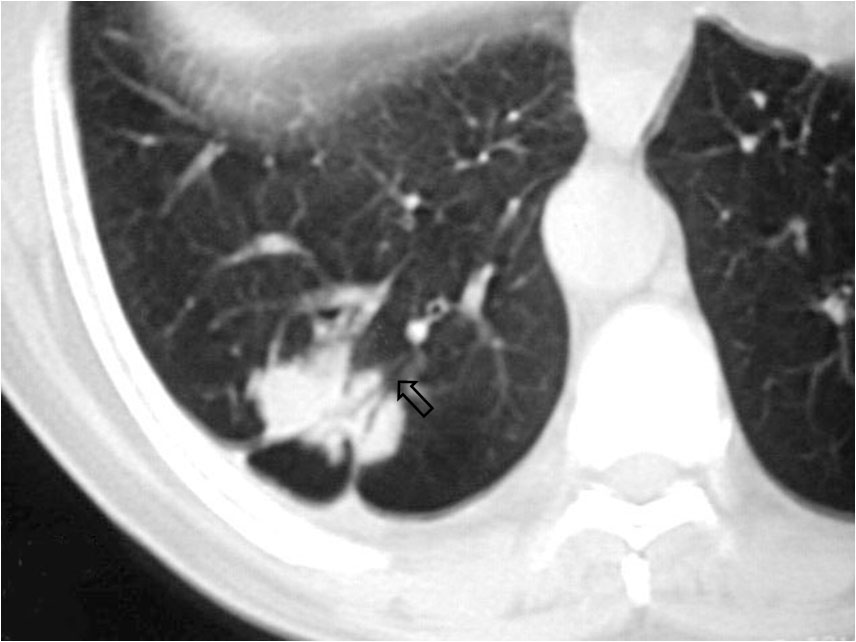

SIGNO DEL BRONQUIO ABIERTO O BRONQUIO POSITIVObronqposHallazgo visible en la TC de tórax que consiste en una imagen de hipodensidad tubular (el bronquio) que alcanza directamente un nódulo pulmonar periférico, en el que puede adentrar  (creándose un signo de broncograma aéreo) o no. En la imagen vemos el bronquio positivo –flecha- y el broncograma aéreo en el interior del nódulo.

Este signo no es específico de malignidad, ya que también está presente en lesiones benignas, como tuberculomas, masas inflamatorias o infartos. Más bien, la utilidad del signo reside en que, cuando está presente, la biopsia transbronquial está indicada y será muy probablemente rentable. Por el contrario, cuando no está presente, la biopsia transparietal es el mejor método para la confirmación histológica.

Ver más en: Singh, SP. The positive bronchus sign. Radiology 1998; 209: 251-252.